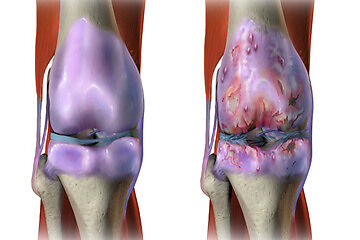

Osteoarthritis is a type of arthritis occurring when flexible tissue at the ends of bones wears down. It commonly affects joints in the hands, knees, hips, and spine.

OA occurs when the cartilage cushioning the ends of bones gradually deteriorates. It causes changes in bone and deterioration of connective tissues, along with joint lining inflammation.